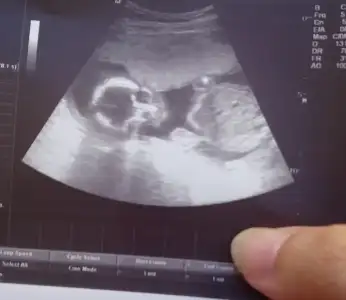

Valla hiçbirşey anlamadım toplasan 5 dk bakmadilar sinir oldum çıktım güya özel hastaneye gittim tip a gitseydim diye pişman oldum sadece bacak karin ölçümlerine baktı eli yüzü düzgün kalbi güzel atiyo dedi cinsiyet kesin kız dedi zaten simsiyah ekrandi göremedim hiçbirşey.tekrar kadin dogumcuya gidip ben yüzünün fotosunu istiyorum hicbisi göremedim dedim oda bu fotoyu verdiler:KK61::kızgın:tam 6 haftadır bugünü bekliyodum resmen hayal kırıklığına uğradim.yine 1 hafta geriden geliyo 286 gr 21 cm ymis

Eklentiler

• _20180404_171552.webp

_20180404_171552.webp

10,9 KB · Görüntüleme: 105